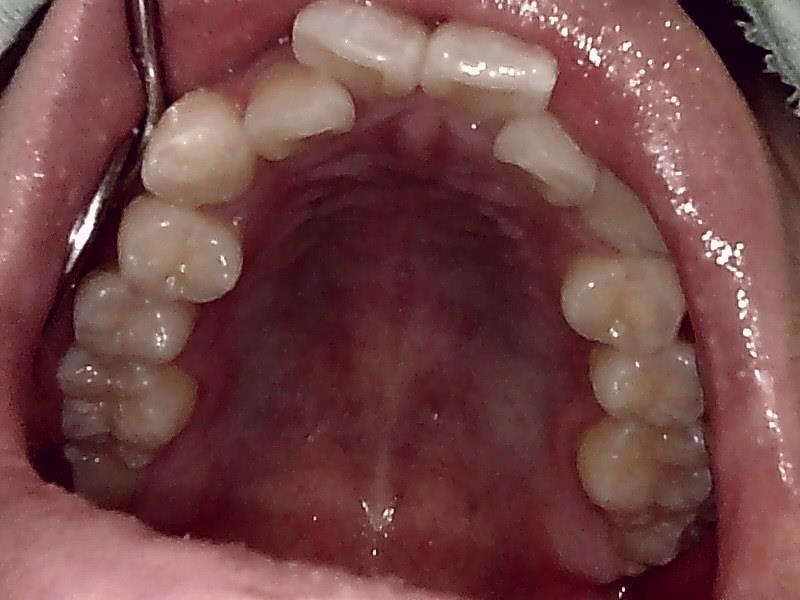

上顎咬合面観